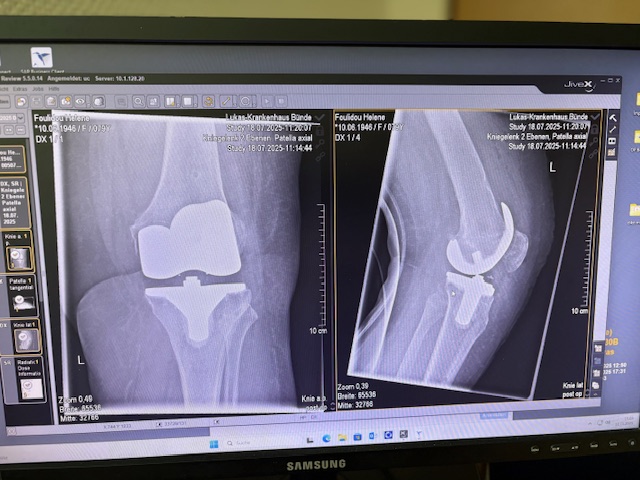

Τα εμφυτεύματα που χρησιμοποιήθηκαν στο γόνατο της ασθενούς είναι της Aesculap: E-Motion Pro, μηριαίο μέγεθος 4, κνημιαίο μέγεθος 4, με ενθέμα (inlay) 10mm.

Η ασθενής κινητοποιήθηκε την ίδια ημέρα μετά την επέμβαση και εξήλθε από το νοσοκομείο την πέμπτη μετεγχειρητική ημέρα.

Ήδη από τις πρώτες εβδομάδες, περπατούσε χωρίς πόνο, με βελτιωμένο εύρος κίνησης.   Η παθητική κίνηση κατα την έξοδο της ασθενούς από την κλινική ήταν E/F : 0-0-120 Επίσης πλήρη σταθερότητα του γόνατος σε κάμψη και έκταση.

Η ακρίβεια του ρομποτικού σχεδιασμού οδήγησε σε άριστη ευθυγράμμιση και φυσική κίνηση, επιτρέποντάς της να επιστρέψει γρήγορα στις καθημερινές της δραστηριότητες και να απολαμβάνει ξανά ποιότητα ζωής και ελευθερία κίνησης!!!